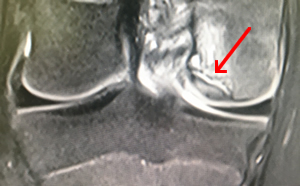

L'ostéochondrite est une maladie de l'os, qui entraine son affaiblissement localisé. Il en résulte un séquestre, petit fragment d'os, qui se "rétracte" et se détache du reste de l'os. Le cartilage en regard est malmené et peut se fissurer. Le séquestre risque alors de sortir dans l'articulation, source de douleurs et ou de blocage.

Noter que souvent le séquestre est tout petit. Il est en général recouvert d'une fine couche de cartilage.

Souvent découverte sur une IRM

Une radio ou une IRM réalisée devant des douleurs de genou, fera la découverte de l'ostéochondrite. Il n'est pas toujours facile de certifier que les douleurs ressenties sont liées à l'ostéochondrite. Elles peuvent être des douleurs rotuliennes banales.

En cas de douleurs persistantes, de doute sur la responsabilité du séquestre dans les douleurs, il est logique de rechercher sur l'IRM ou sur un Arthroscanner (scanner avec injection d'un produit de contraste), des signes évoquant une fissure du cartilage recouvrant le séquestre : le liquide articulaire pénètre alors dans la niche osseuse, entourant plus ou moins le séquestre.